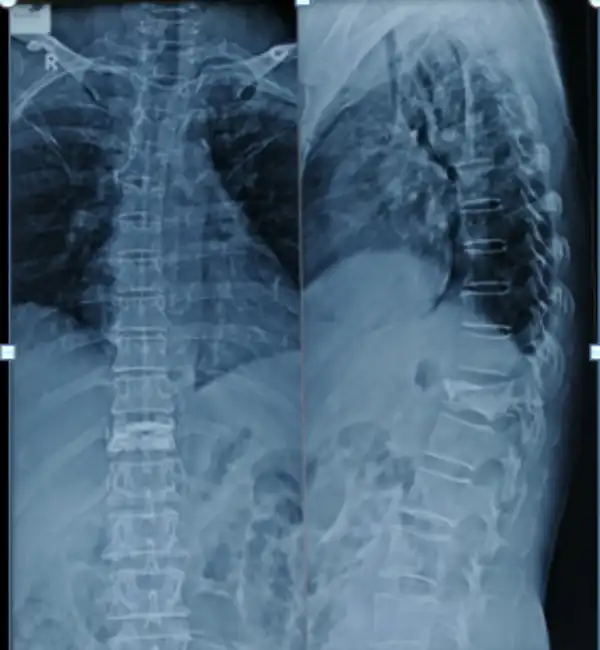

Multi level fracture Pre Op X ray

Multilevel vertebroplasty Post Op x ray

MIS Stabilization Vertebroplasty

Vertebroplasty With Instrumentation